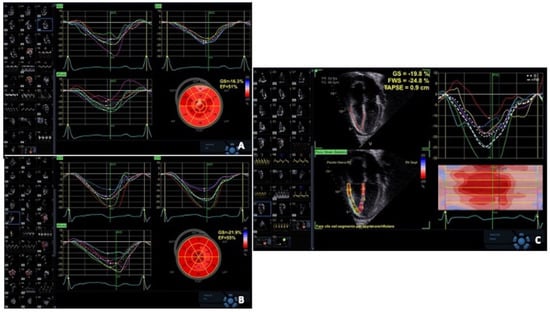

| Mingo-Santos et al. [57] | LV GLS < 15.5% RV FW < 17% LV + RV | 34 | ≥2R | 85.7 85.7 100 | 91.1 81.4 77 | 98.8 98.8 100 |